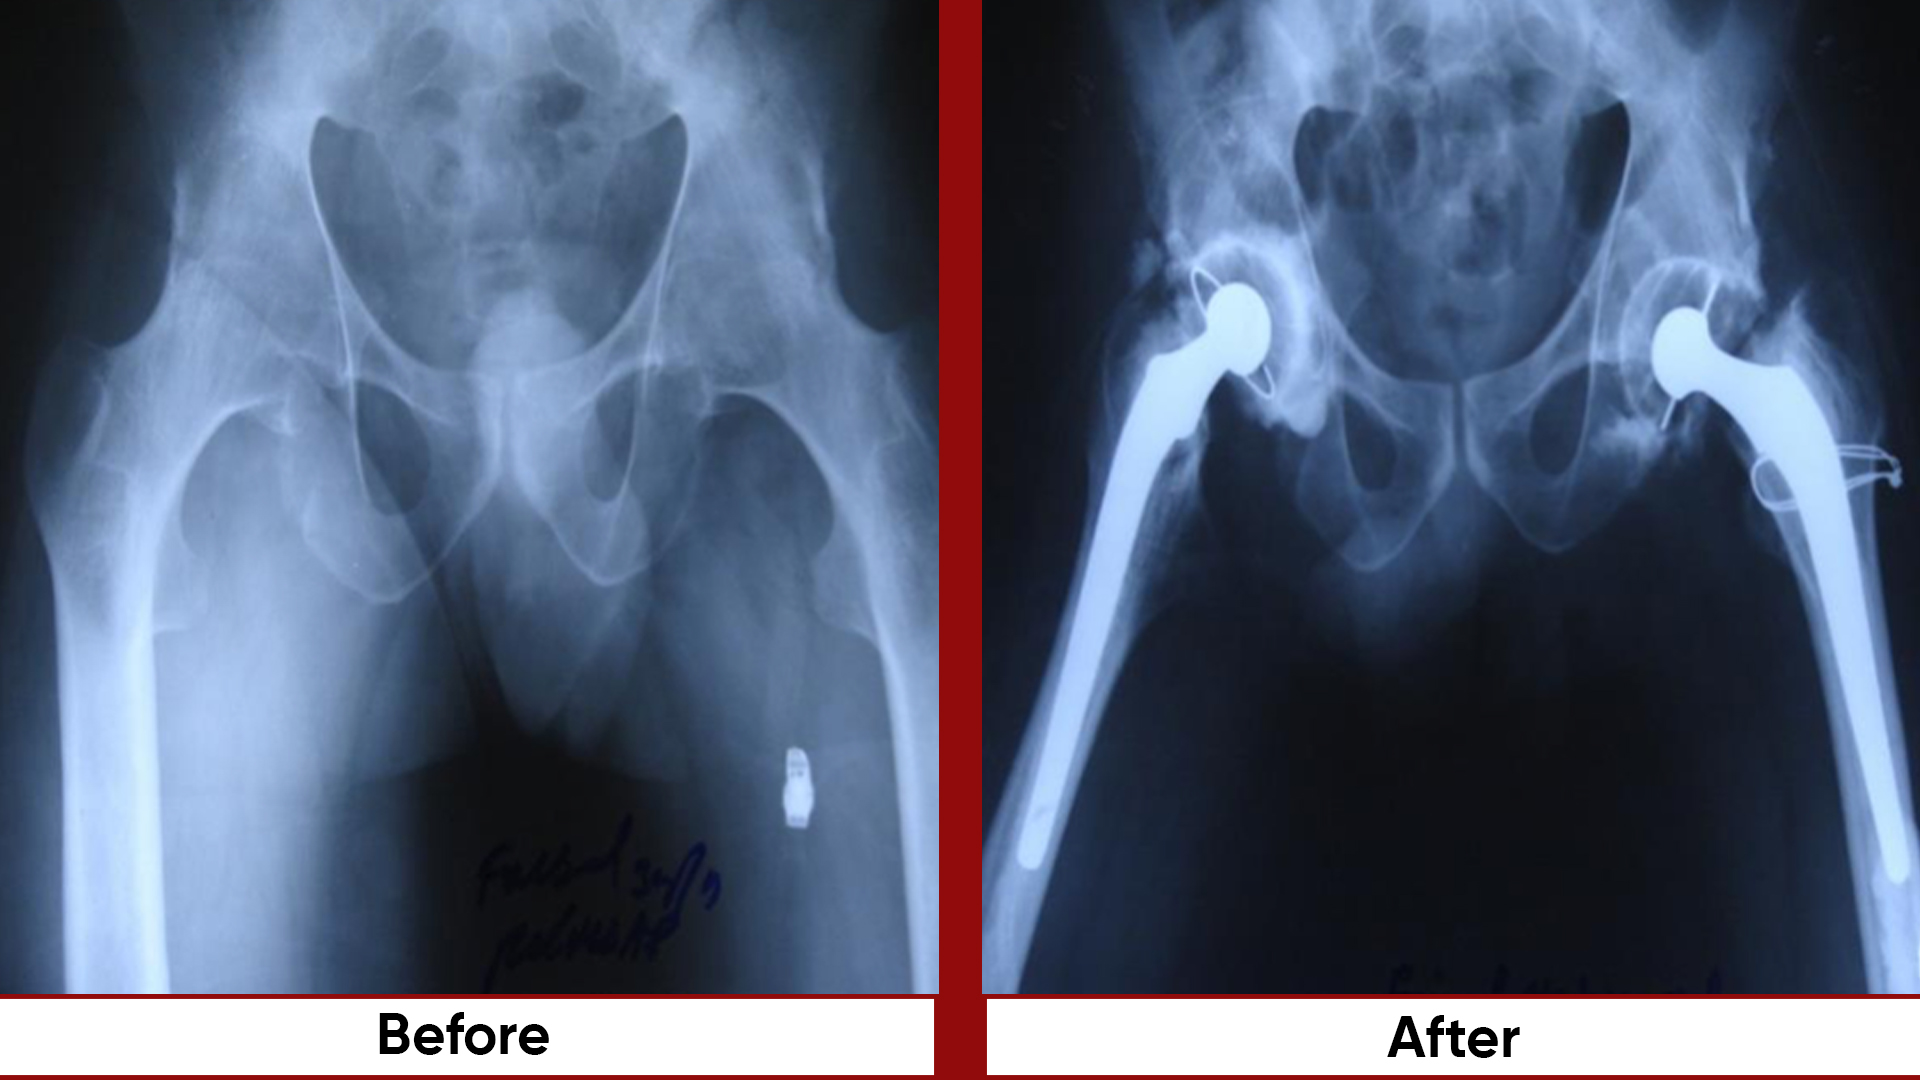

• Total Hip Replacement (THR)

• Pelvic & Acetabular Fracture Fixation